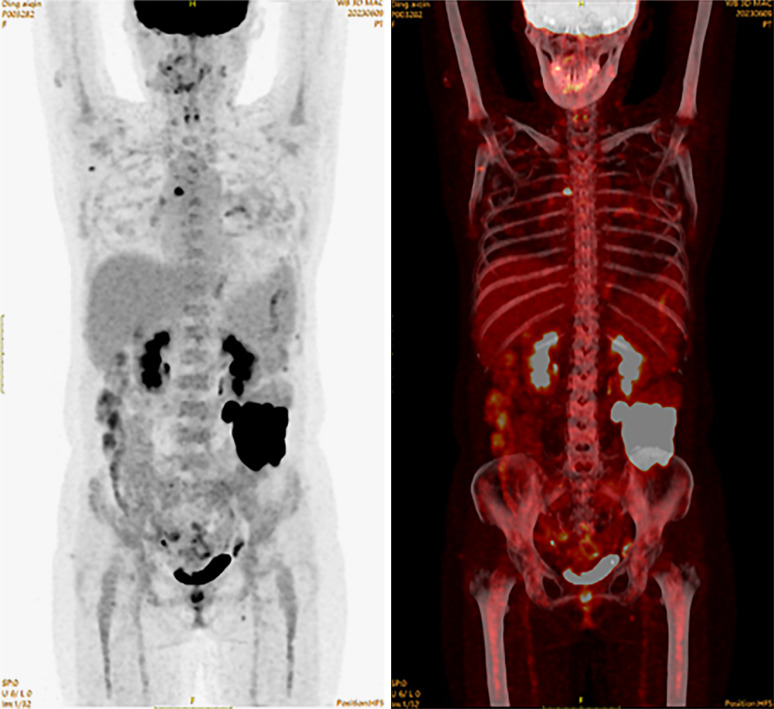

Case presentation: We report the case of a 47-year-old woman who presented with a 2-month history of left lower abdominal pain and discomfort. Imaging studies, including enhanced abdominal CT and PET-CT, revealed a suspicious mass in the jejunum. Comprehensive diagnostic evaluations excluded metastatic origins, and a diagnosis of primary small intestinal SCC was confirmed by histopathology and immunohistochemistry. The patient underwent radical surgical resection, which revealed a poorly differentiated SCC invading the serosa and regional lymph nodes. Postoperative management included infection prevention and fluid rehydration, with recommendations for adjuvant chemotherapy and immunotherapy based on multidisciplinary consultation. Despite the advanced disease stage, the patient recovered well post-surgery and is undergoing regular follow-up.